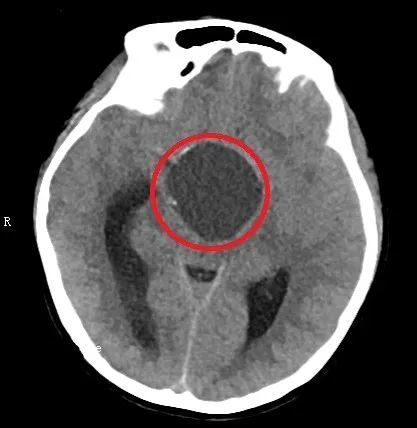

术后头部CT显示:鞍区肿瘤基本切除干净。(红圈内为手术区域)